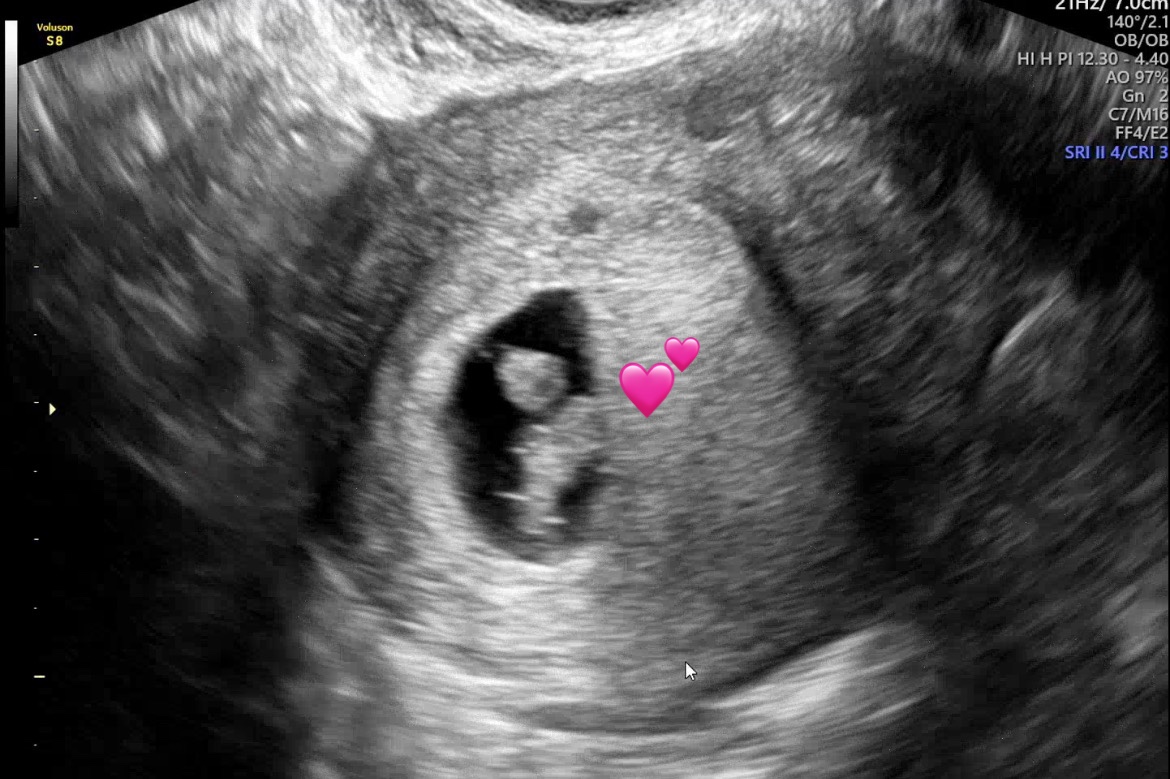

| 치료 도중 느꼈던 가장 기뻤던 순간과 절망적인 것들은 무엇인가요? 잊지 못할 경험이 있나요? | 가장 기뻤던 순간은 1차 피검사에서 처음 임신 수치(66)를 확인했을 때였습니다. 드디어 기다리던 반응을 본 그날은 정말 감격스러웠어요. 하지만 3일 후 2차 피검사에서 수치가 더블링되지 않아 너무 큰 실망과 좌절감을 느꼈습니다. “이번에도 안 되는 건가…” 하는 생각이 들며 마음이 완전히 무너졌던 순간이었어요. 그래도 다행히 이유정 원장님께서 “조금 지켜보자”고 말씀해 주셔서 그 말을 붙잡고 1주일을 간절한 마음으로 보냈고, 결국 아기집을 확인할 수 있었습니다! 살면서 이렇게 기쁨과 불안이 동시에 밀려오는 ‘양가감정’을 느껴본 적이 없었던 것 같아요. 그리고 또 그다음 1주일, 또 그다음 1주일… 정말 길고 숨 막히는 시간들이었지만, 초음파에서 조금씩 자라고 있는 아기집과 아기를 볼 때마다 세상에 다시 감사하는 마음이 들었습니다. |